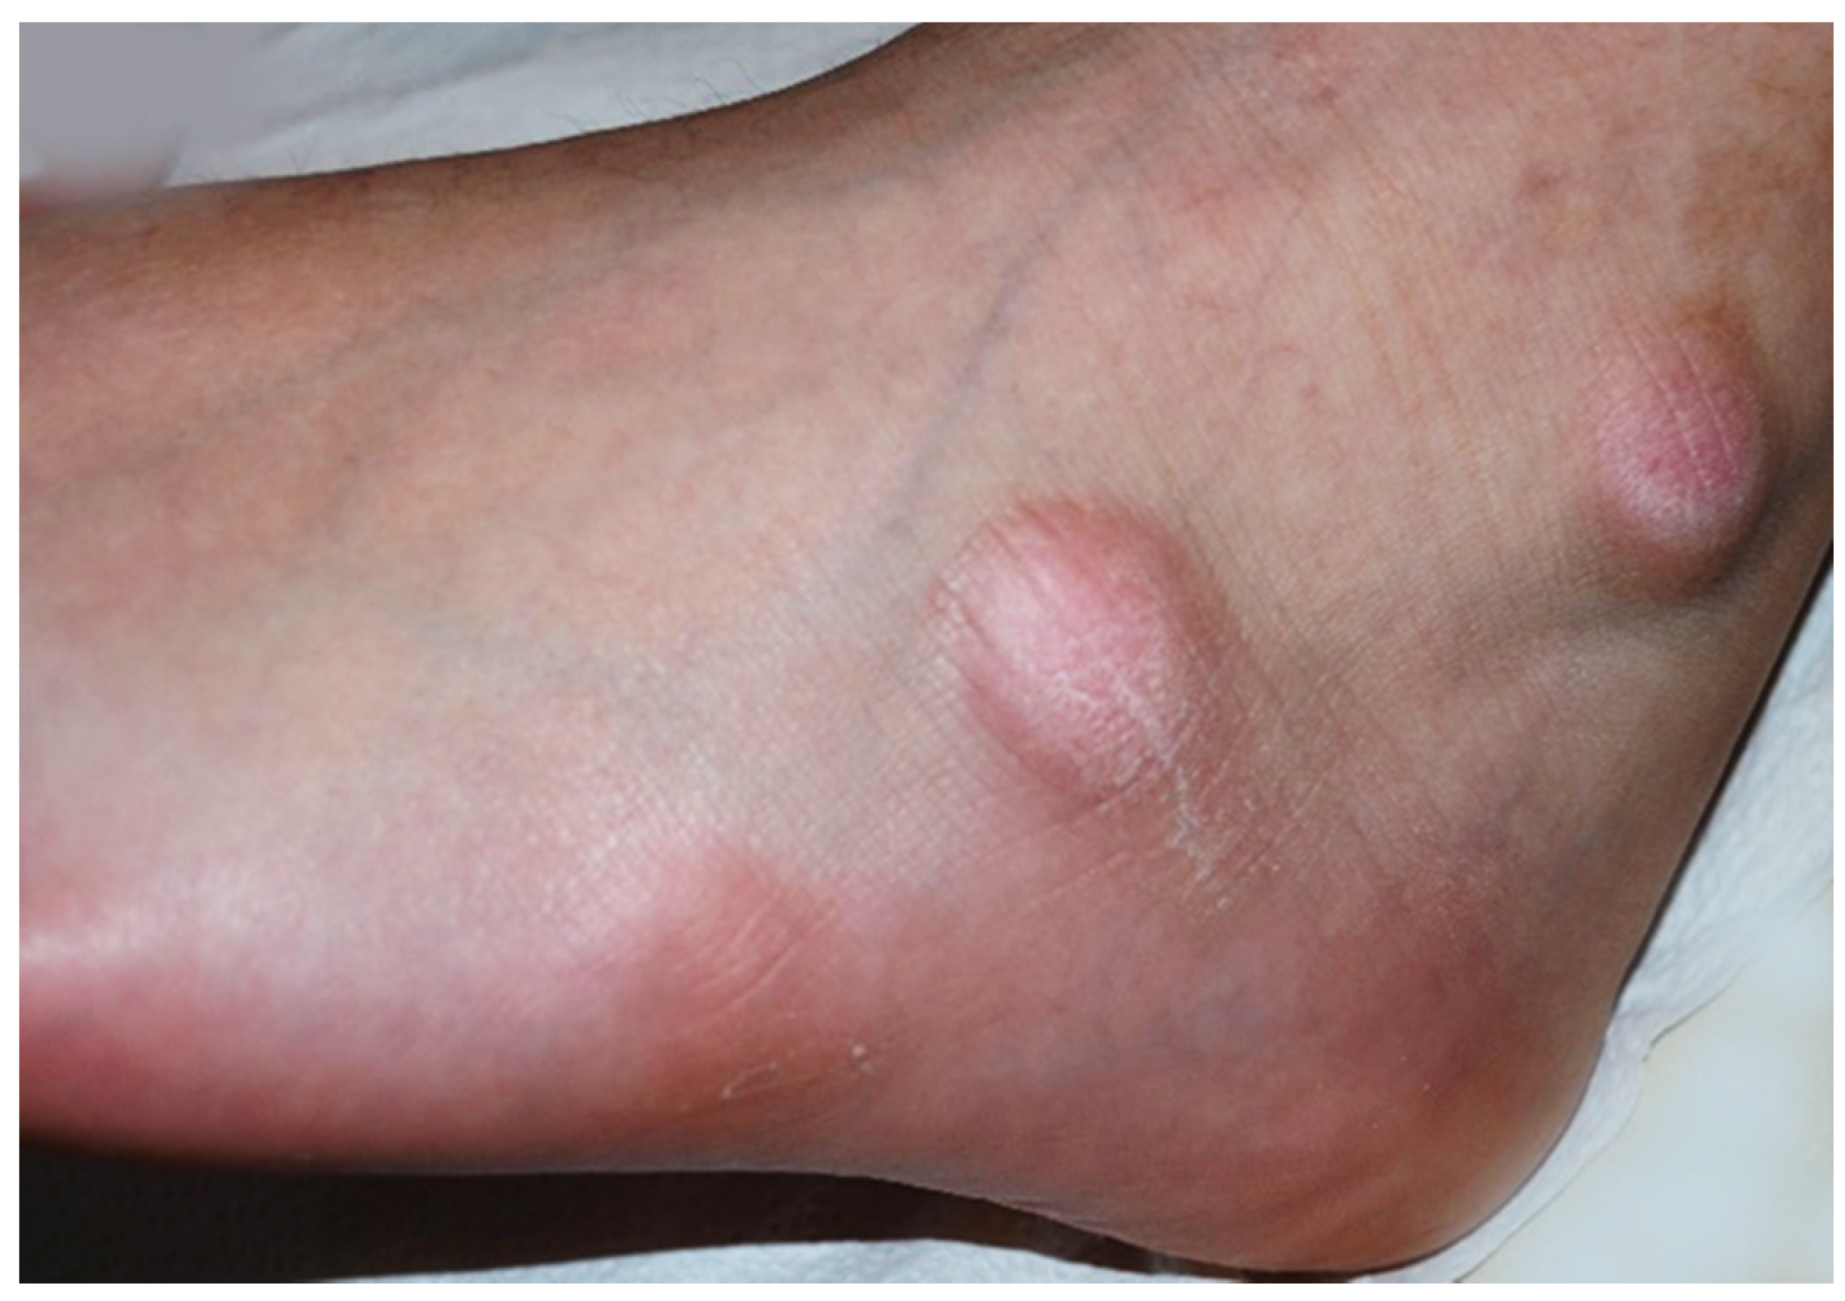

Figure 1.

Asymptomatic firm nodules measuring 2–3 cm in diameter on the lateral aspect of the left foot.